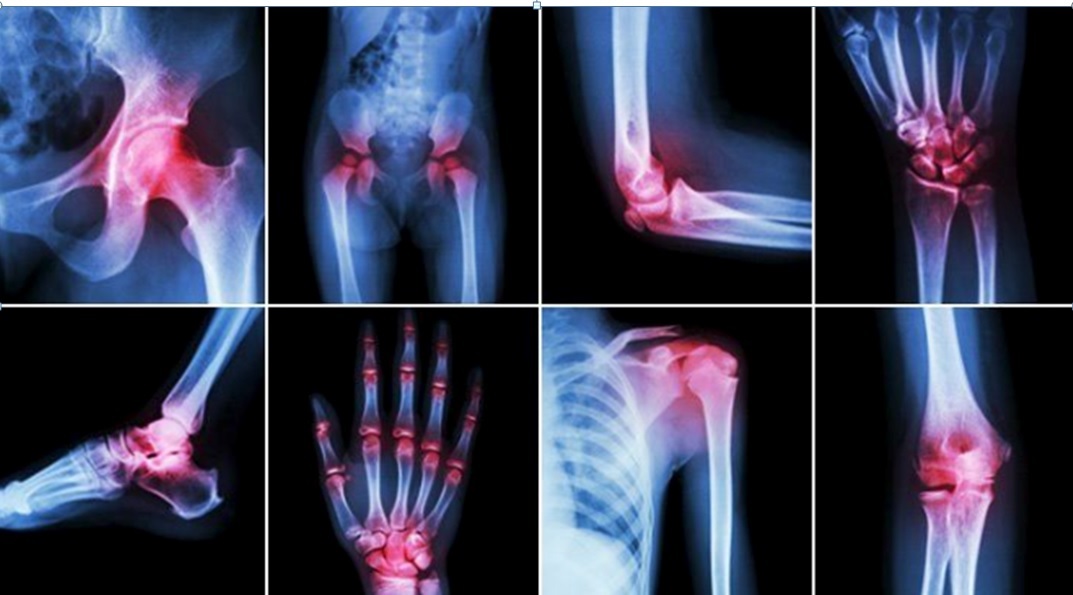

Ένας στους έξι Έλληνες πάσχει από αρθρίτιδα, μια κλινική οντότητα που καλύπτει ένα ευρύ φάσμα παθήσεων από την οστεαρθρίτιδα και την ουρική αρθρίτιδα ώς την ρευματοειδή αρθρίτιδα και την ψωριασική αρθρίτιδα. Πλέον των 80 παθήσεων εμφανίζουν αρθρίτιδα, πολλές από τις οποίες είναι αυτοάνοσα ρευματικά νοσήματα που χρειάζονται ιδιαίτερη προσοχή. Η έγκυρη και έγκαιρη διάγνωση και η πρώιμη έναρξη αποτελεσματικής θεραπείας και πρώιμης αντιμετώπισης αποτελεί «κλειδί» για την ύφεση των συμπτωμάτων και τον πλήρη έλεγχο της προόδου της νόσου.

Μια πληθώρα από παθήσεις ενφανίζονται με αρθρίτιδα, πόνο και ευαισθησία στις μικρές και μεγάλες αρθρώσεις που οδηγούν σε δυσκαμψία, επηρεάζουν την κινητικότητα και την ποιότητα ζωής εκείνων που πάσχουν. Φέτος και εν μέσω της πανδημίας COVID-19 οι Ελληνίδες και Έλληνες που πάσχουν από αρθρίτιδα κάθε μορφής, σε χρειάζονται. Δείξτους ότι τους σκέφτεσαι, ότι μοιράζεσαι τις ανησυχίες τους και τον πόνο τους. Φορέσαι μπλε καθ’όλη τη διάρκεια του μήνα για να υποστηρίξεις με τον πιο απλό τρόπο την ευαισθητοποίηση για την ασθένεια που προσβάλει 1.5 εκατομμύριο Ελληνίδες και Έλληνες κάθε ηλικίας.